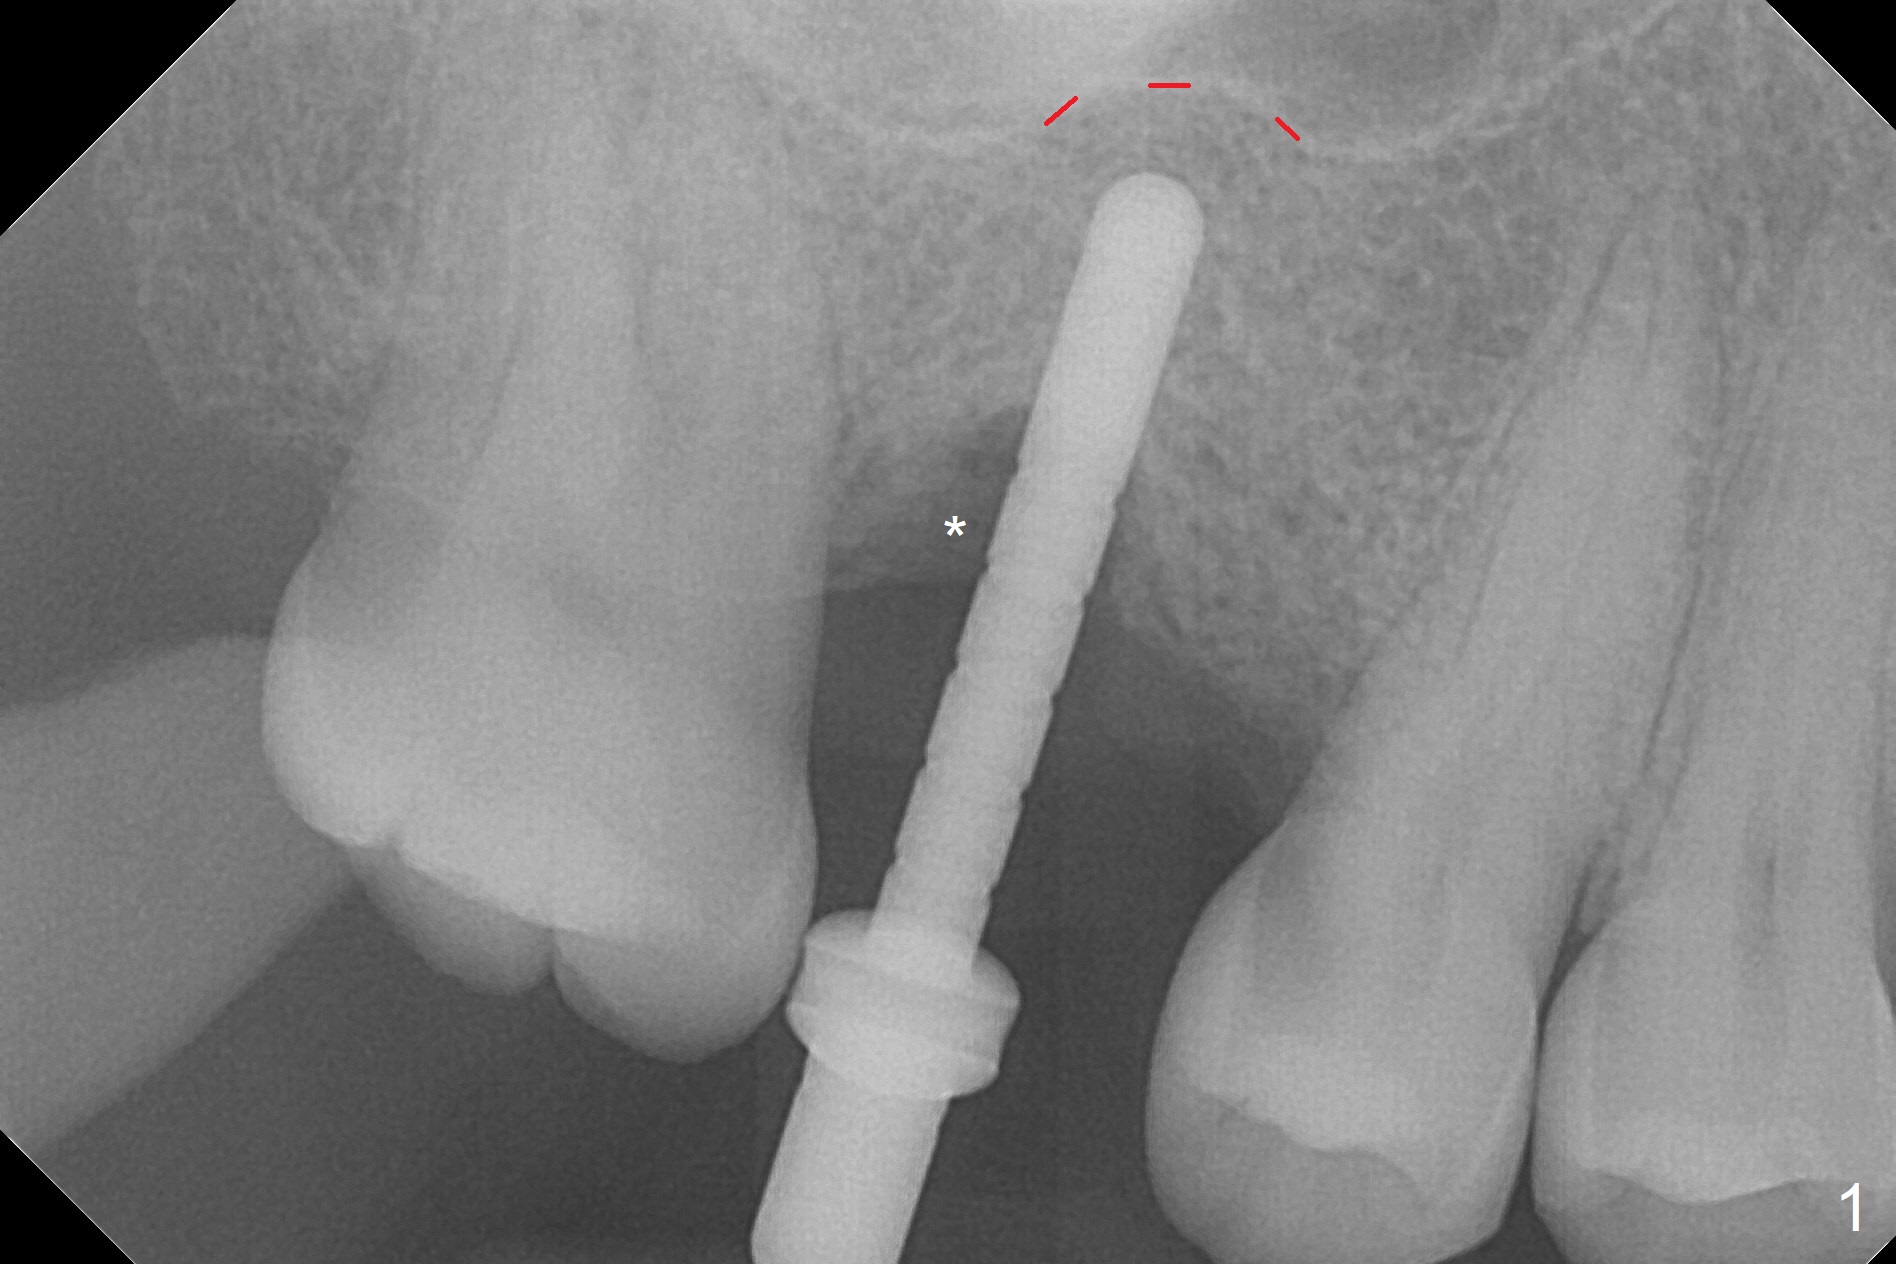

There are 2 sockets at #3 when the residual roots are extracted; osteotomy is established in the palatal one for 11 mm (gingival level; Fig.1), ~ 2 mm from the sinus floor (red dashed line). Following the last drill (3.8 mm) for 11 mm, a 4.5x11 mm dummy implant is placed 2 mm subgingival (Fig.2). In fact the sinus lift (red dashed line) is done by implant insertion, since the bone plug after Magic Drill is present in the apical portion of the osteotomy when the last drill is finished prior to implant placement.. After the dummy implant is removed, the definitive one (the same size) is placed with >50 Ncm, followed by placement of a 4.5x4(3) mm abutment and VeraGraft mixed with autogenous one (Fig.3 *). The most coronal portion of the socket is sealed with collagen plug. The latter is fixed in place by an immediate provisional. The mesial surface of the tooth #2 is reduced (Fig.4 <) prior to provisional fabrication. The implant is placed distal, which could be corrected by pushing the 2nd molar distal orthodontically. There is mild crestal bone loss nearly 8 months postop (Fig.5). An angled abutment (5x15 degrees, 3 mm cuff) is used before impression. CT is taken immediately post cementation (Fig.6 (8.5 months postop)). CT taken 8 months post cementation shows that the 4.5x11 mm implant barely passes the sinus floor (Fig.7). Return to Upper Molar Immediate Implant, Prevent Molar Periimplantitis (Protocols, Table), IBS, 30 19 Xin Wei, DDS, PhD, MS 1st edition 09/13/2017, last revision 01/31/2019